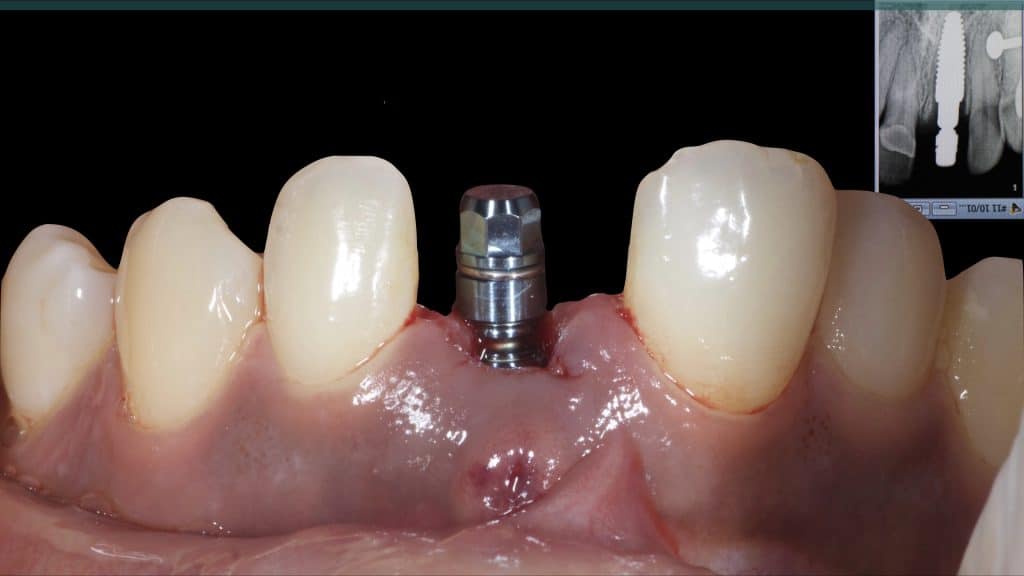

A 27-year female patient with dislodged Resin bonded FPD. She had that FPD for past few years, it had metal wings on palatal surfaces of UR1 and UL2 and a post like metal extension into the root canal of UL1. There was gingival abscess due to fractured root segment most probably due to extended metallic post like structure. Immediate implant placement (IIP) and Immediate restoration (IR) was planned for this patient.

20 days post-op after suture removal